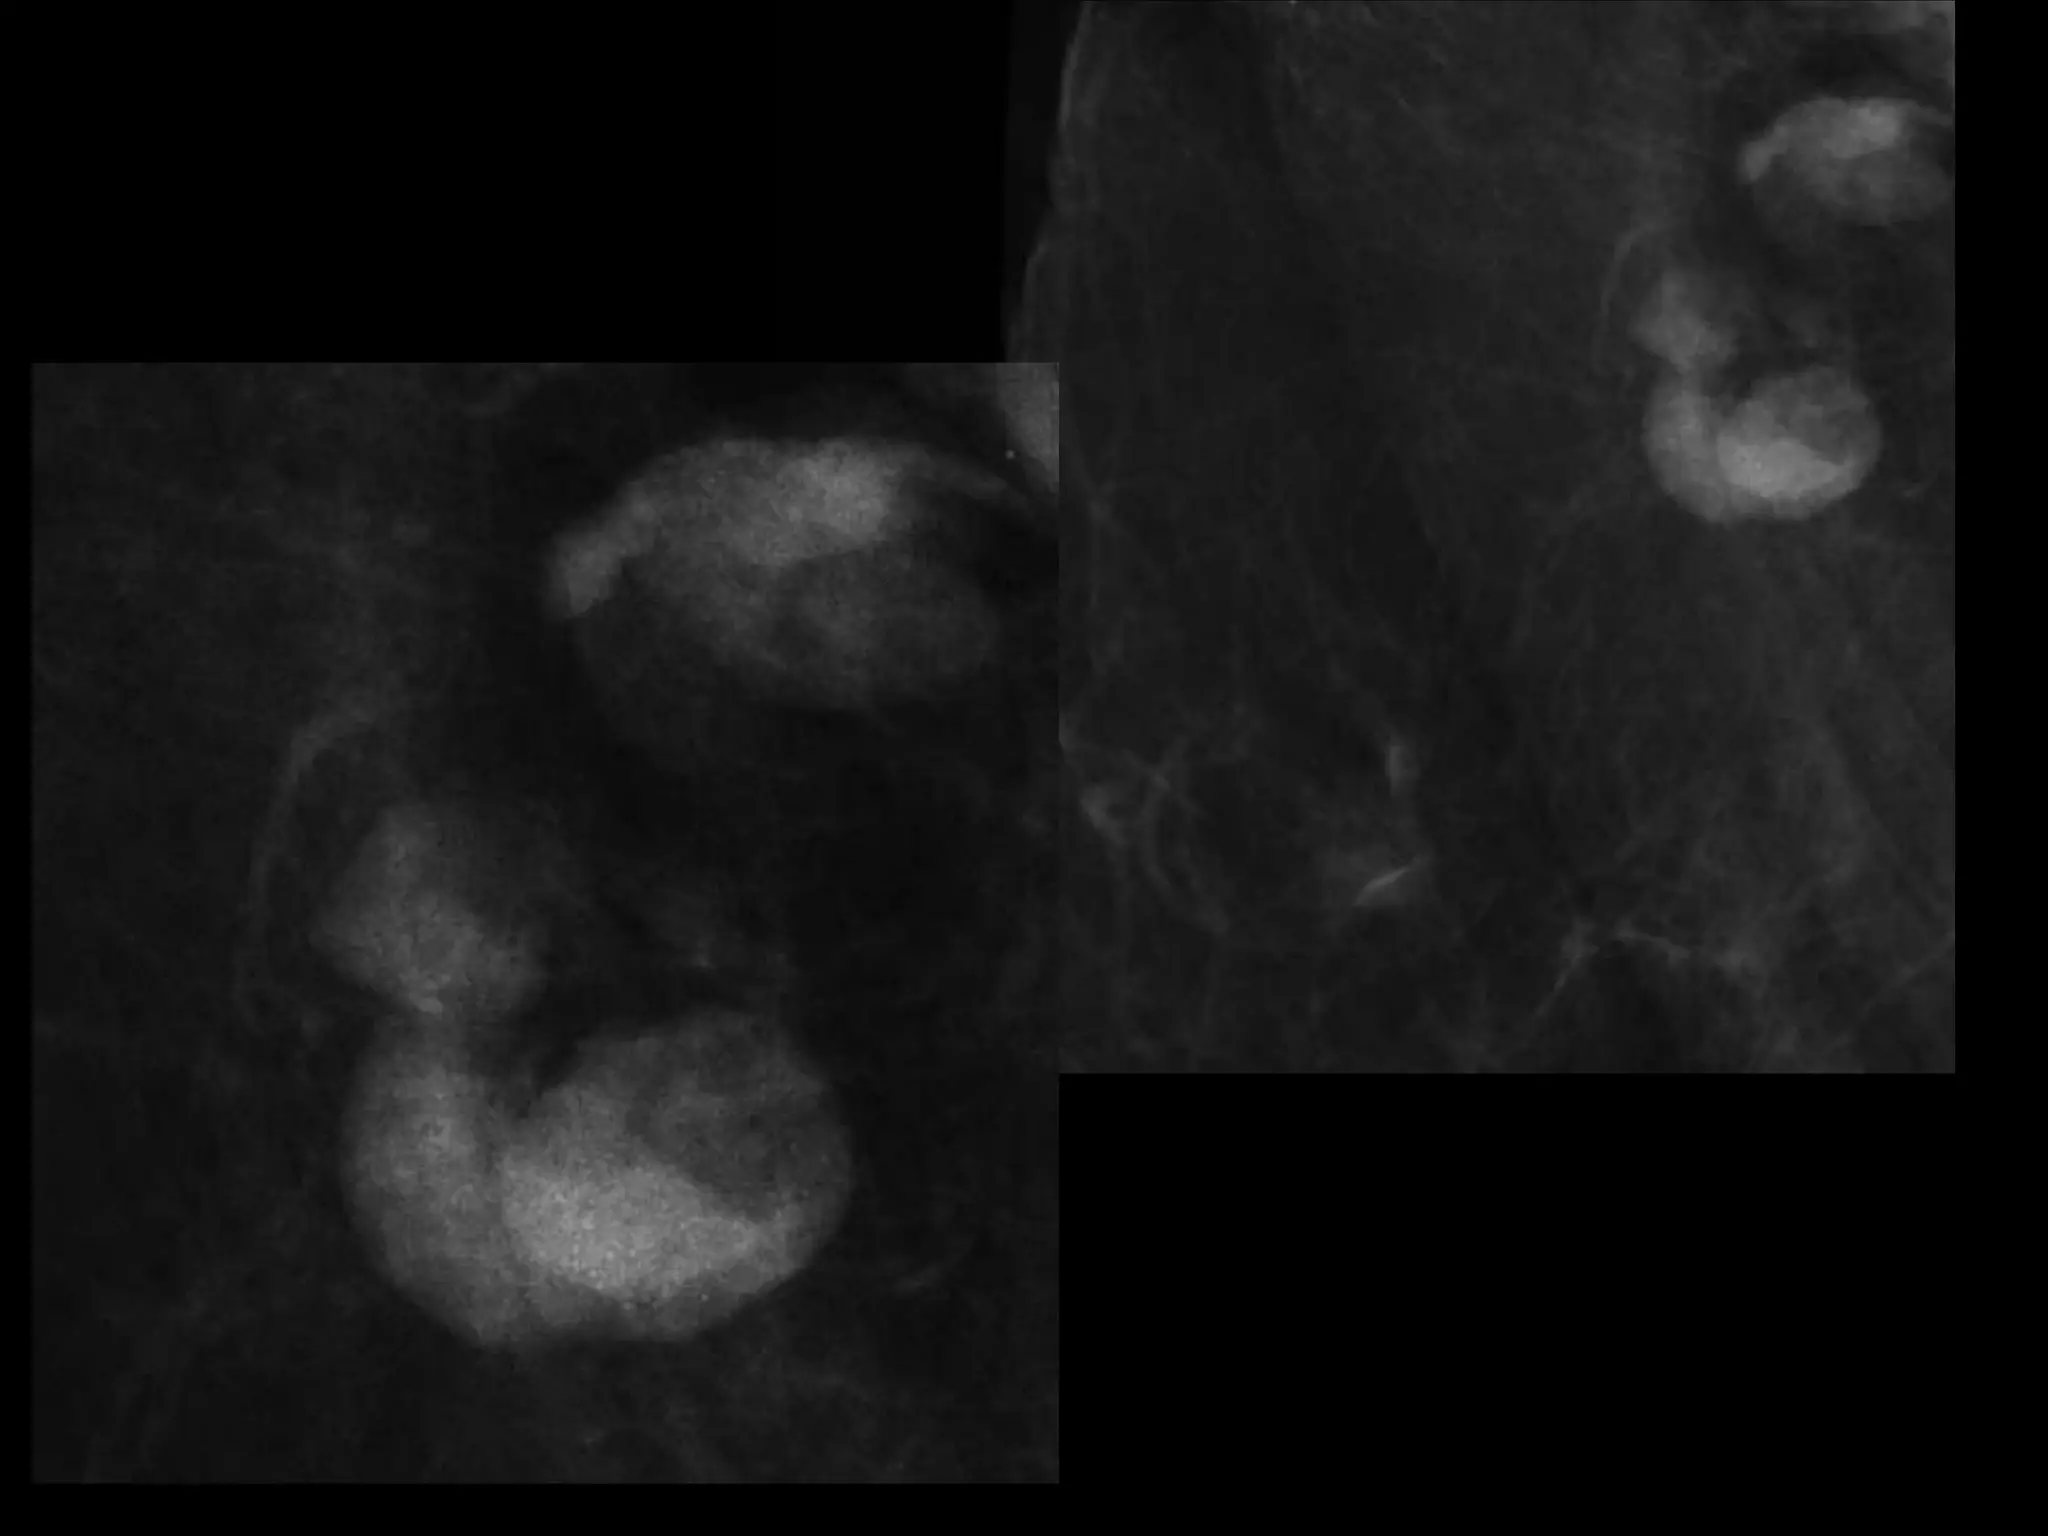

Dr. Hedvig Hricak

HISTORY

โ€ข   42 yo female

โ€ข   Recent immigrant from China

โ€ข   C/O postcoital and intermenstrual bleeding

โ€ข   Abnormal GYN exam

โ€ข   Abnormal biopsy

โ€ข   Further imaging performed

MRI findings - Stage IIB

with PET/CT - Stage IIIB

HISTORY โ€ข 42 yo female โ€ข Recent immigrant from China โ€ข C/O postcoital and intermenstrual bleeding โ€ข Abnormal GYN exam โ€ข Abnormal biopsy โ€ข Further imaging performed

• 63.

MRI findings -Stage IIB with PET/CT - Stage IIIB Cervical Cancer

Role of MRImaging in Tx Stratification of GYN (Cervical) Cancer โ€ข Cervical Cancer โ€“ 2nd most common ca in women worldwide โ€“ Developing countries; pk 30-40 yrs โ€ข FIGO classification โ€“ revised in 2009 from just clinical to incorporate cross-sectional imaging (CT, MR) โ€ข Staging accuracy of MR 85-96% โ€“ Best test to assess tumor size and location; invasion into parametria, pelvic side wall, adjacent organs; local nodal enlgment โ€ข PET/CT helpful in staging advanced disease โ€“ Demonstrates unexpected sites beyond pelvis โ€ข Treatment options โ€“ Radical surgery - early stage (IA, IB1, IIA1) โ€“ Primary Chemo and Radiation โ€“ bulky IB2 or IIA2, or local advanced (IIB or greater) Sala et al. Radiology 2013; 266: 717.